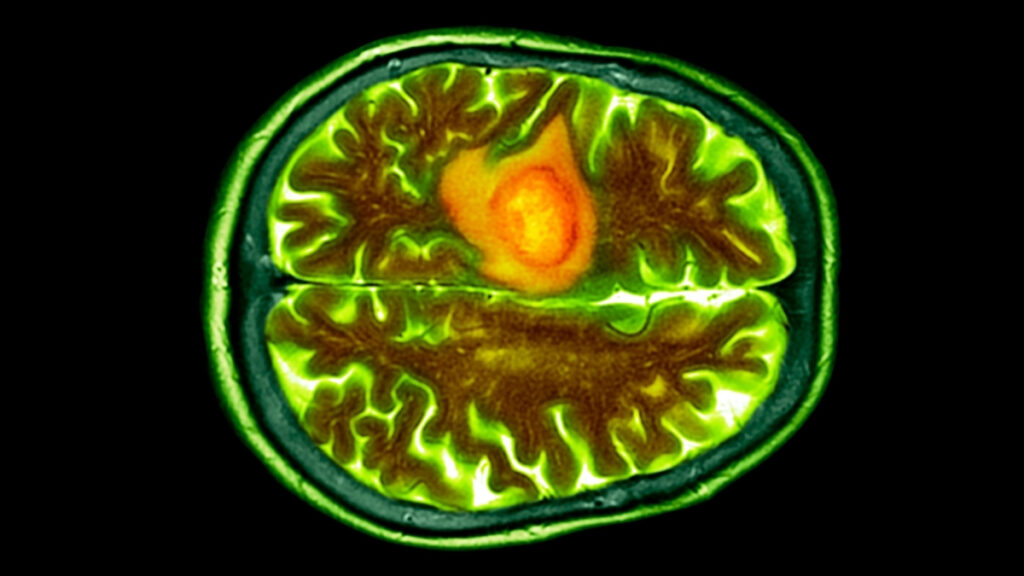

به گزارش سیناپرس، یکی از مرگبارترین انواع سرطان مغز، گلیوبلاستوما (Glioblastoma) نام دارد که متاسفانه شایعترین سرطان بدخیم مغز بوده و تنها ۶٫۹ درصد بیماران بیش از پنج سال پس از تشخیص زنده میمانند.

به گفته محققان، سرطان گلیوبلاستوما بسیار مهاجم بوده و در مراحل اولیه بهسختی تشخیص داده میشود و متاسفانه سیستم ایمنی بدن را فلج میکند. به همین دلیل درمانهای معمولی سرطان تقریباً در برابر آن بیاثرند. این تومور در مغز یا دیگر نقاط حساس سیستم عصبی مرکزی رشد کرده و به همین دلیل دسترسی مستقیم به آن بسیار دشوار و خطرناک است. این نوع سرطان همچنین با ایجاد تورم، فشار آوردن به بافتهای سالم اطراف و دزدیدن خون آنها، عملکرد مغز را بهسرعت مختل میکند.